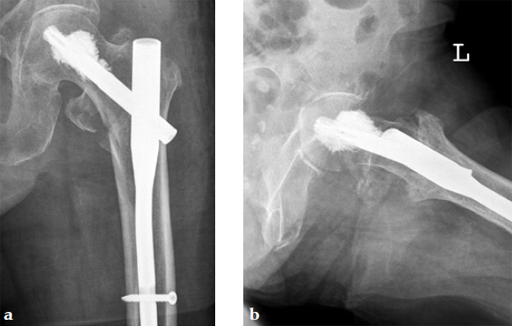

An 82-year-old woman with an unstable pertrochanteric fracture of the right proximal femur. Her Barthel Index was 80 and her preoperative Parker mobility score was 5, which means that she was walking at home unassisted. The patient's preoperative Parker mobility score of 5 was reached again at the 3-month follow-up.

Augmentation of a proximal femoral nail construct